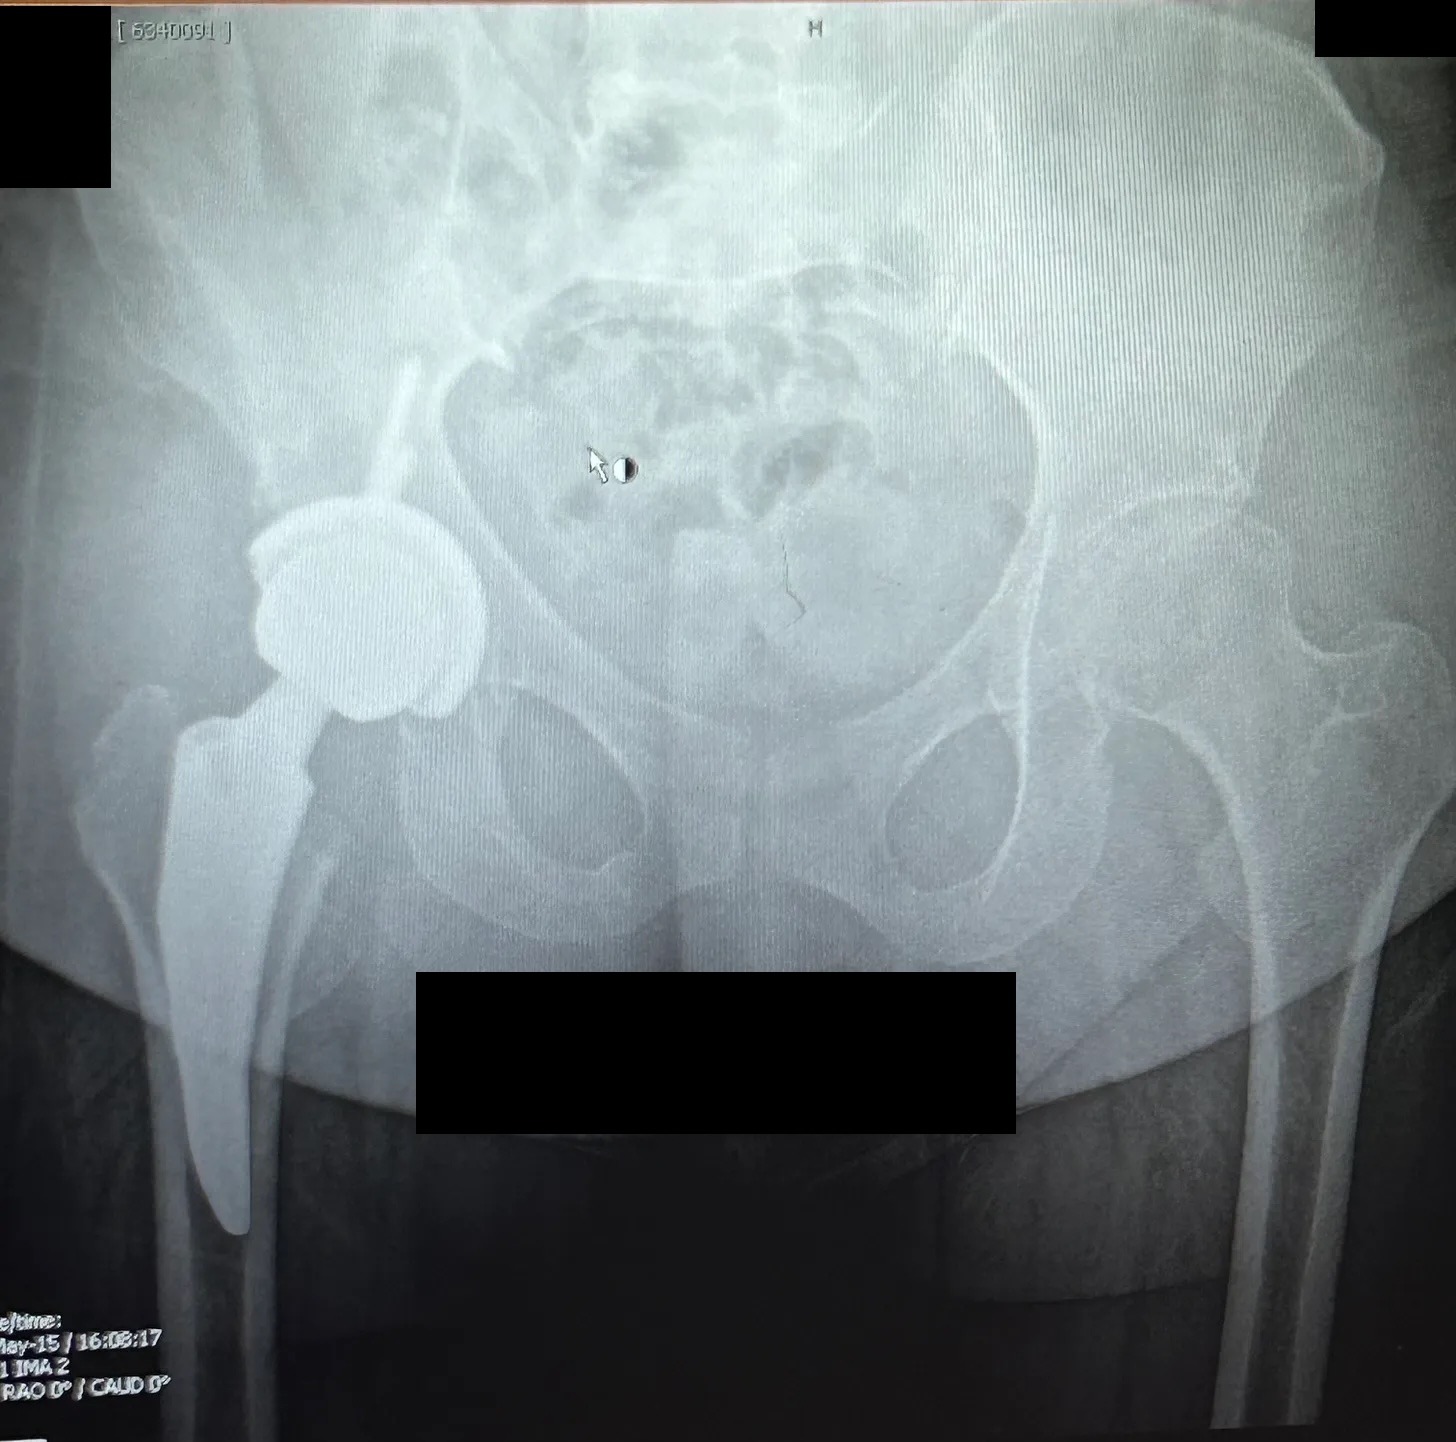

My six-month post-op X-ray. Check out that artificial hip!

1 year since surgery

It’s been one year since my hip replacement. Time is a weird, fluid thing. It feels like it’s only been a few […]